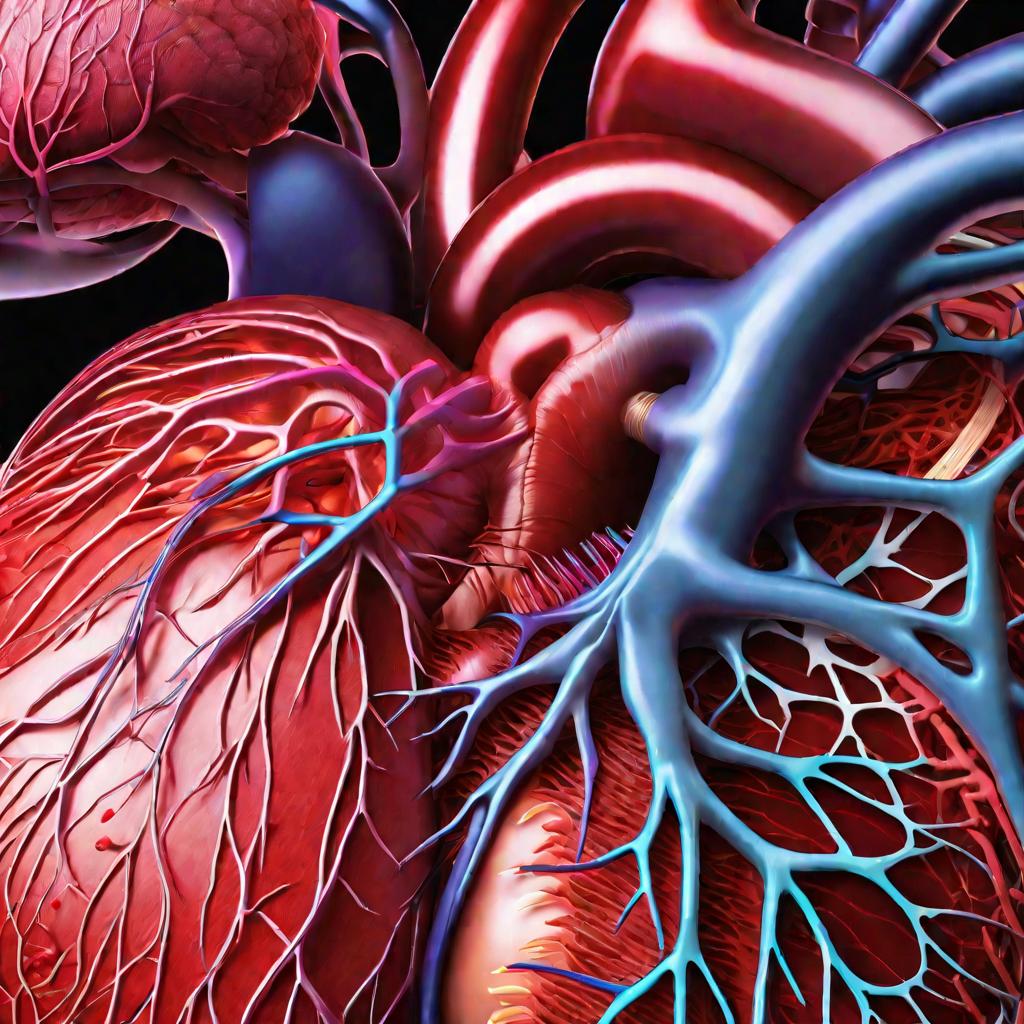

Пороки сердечно-сосудистой системы: виды и признаки